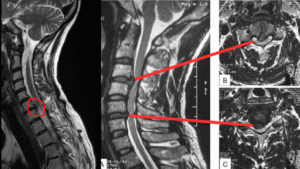

Cervical Disc Herniation Symptoms, Treatment, causes, diagnosis and surgery By Dr. Saijyot Raut, Consultant Spine Surgeon at One Spine 13/11/2025 | 7 Min read Facebook